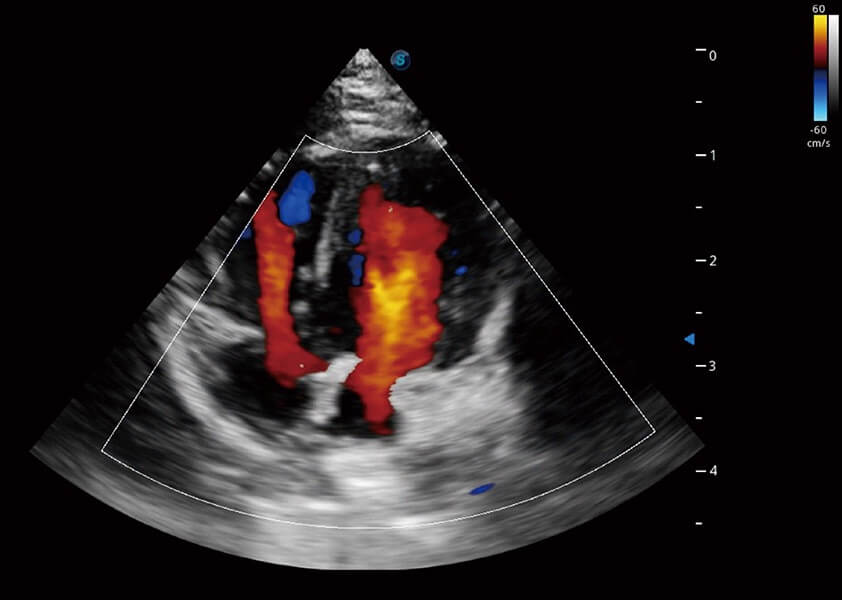

优异的基础图像

(犬)四腔心血流

(犬)肾脏血流